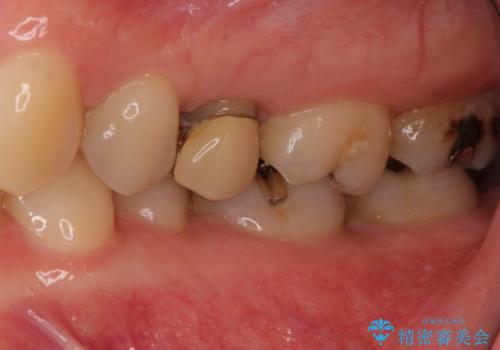

- 銀歯の周りの歯が欠けてしまい、気になるとのことで来院された患者様です。

痛みなどは特になく、診査をしたところ歯の神経に大きな問題はなかったのですが、レントゲン写真より神経に近くに迫るほど大きなむし歯があることが分かりました。

虫歯が歯髄腔(神経の部屋)に達している可能性が非常に高かったため、炎症を起こしている神経組織を部分的に切除し、歯根部分の神経組織を保存する治療法が望ましいと考えられました。

元々の銀歯も大きく装着されていたため、虫歯治療後はセラミッククラウンにて補綴することとしました。